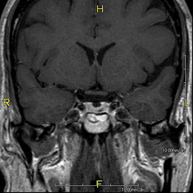

- RM Cerebral (craneal)

Prueba diagnóstica no invasiva que consiste en la obtención de imágenes de alta definición anatómica del cerebro mediante el empleo de un campo electromagnético y ondas de radio (con un emisor y un receptor). No utiliza radiación ionizante. Indicaciones: problemas vasculares, pérdida de memoria, epilepsia, cefalea, malformaciones, sospecha de tumor, meningitis.